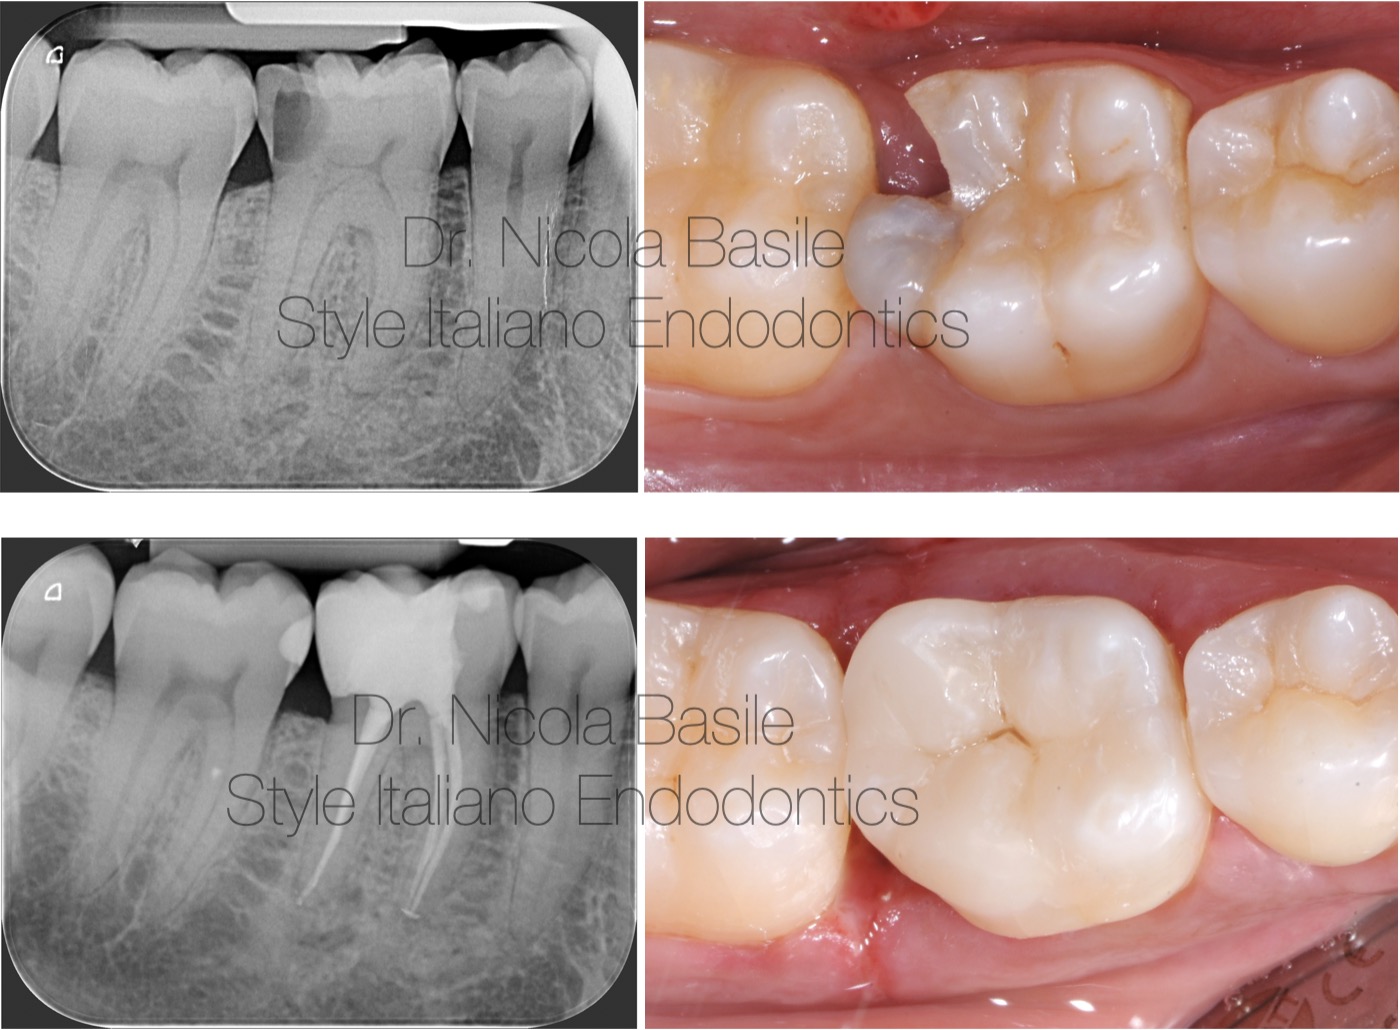

Fig. 1

In this article, a clinical scenario would be presented regarding a patient who lives in another region and returns only a few times a year to their hometown to visit relatives.

During this time, they experience tooth pain and decide to seek treatment at the author’s dental office. All procedures had to be managed within ten days due to the patient’s need to return to their region of residence.

Diagnosis: Large distal carious lesion on tooth 4.6 with pulpitis.

Therapy: Endodontic treatment, clinical crown lengthening, build up and indirect partial crown restoration.

Fig. 2

Shaping was performed using instruments with reduced taper: 30.04 in the mesial canals and 40.04 in the distal canal. Sodium hypochlorite activation was carried out using the gutta-percha cones and the mesial canals were obturated with a single cone and bioceramic cement. The closure of the distal canal was postponed due to bleeding.

Fig. 3